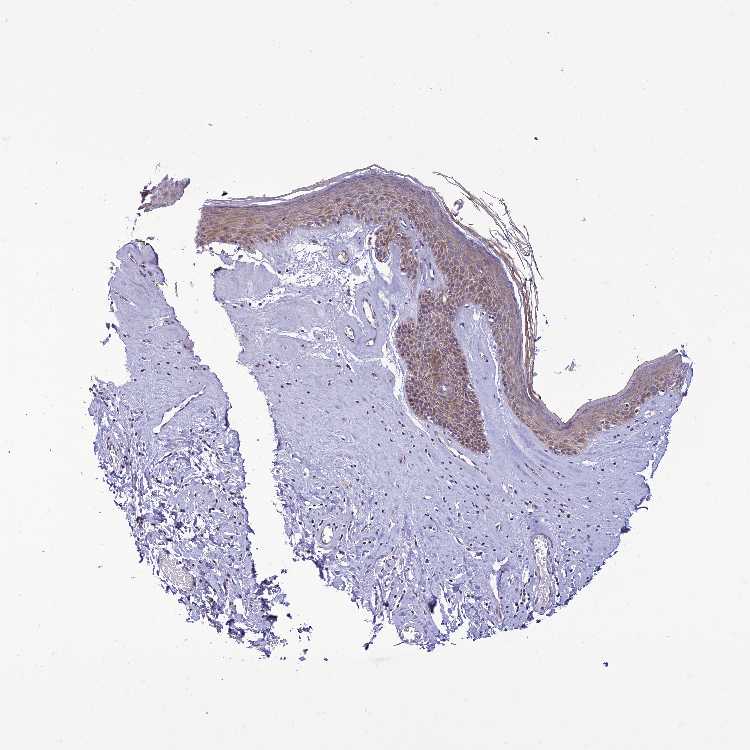

SKIN 2 - Antibody stainingi

Antibody staining in the annotated cell types in the current human tissue is reported as not detected, low, medium, or high, based on conventional immunohistochemistry profiling in selected tissues. This score is based on the combination of the staining intensity and fraction of stained cells.

Each image is clickable and will lead to virtual microscopy that enables deeper exploration of all samples and also displays staining intensity scores, fraction scores and subcellular localization as well as patient and tissue information for each sample.

Antibody HPA044621

Epidermal cells Medium